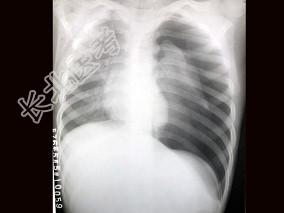

- 单项选择题患者,男, 3岁,突发左侧胸痛伴呼吸困难3小时入院, 如图所示,最可能的诊断为 ( )

A、左侧肺气肿

B、左侧气胸

C、左肺门淋巴结结核

D、右肺小叶性肺炎

E、以上都不正确